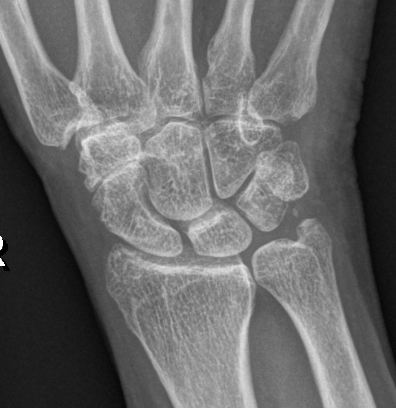

Isolated STT osteoarthritis

OA of the scapho-trapezium-trapezoidal (STT) joints

Third most common wrist osteoarthritis after CMC OA and SLAC wrist

- associated with CMC OA in 60% of cases